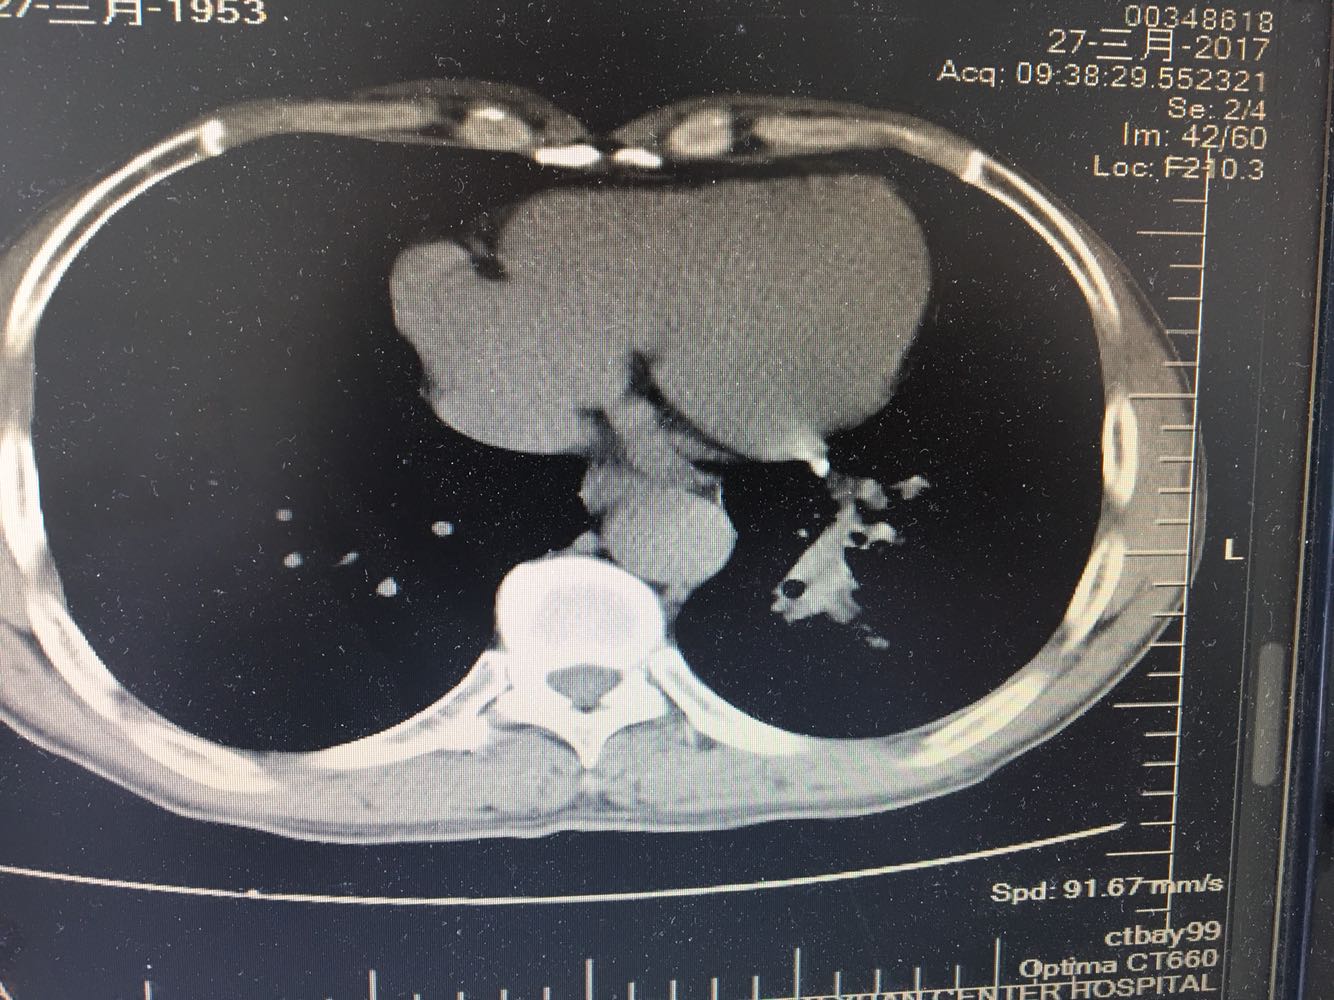

左肺下叶鳞癌

男,63岁,咳嗽1个月入院,患者自述1个月前无诱因咳嗽,阵发性干咳,无痰,时有血丝,无发热,左胸痛,活动后气短,静滴头孢13天无好转,门诊查肺CT后以 肺占位收入我科,病来饮食睡眠可,体重明显下降。既往疝气术后1年,吸烟史30年,每日1包。

左肺癌

左肺中央型肺癌,是否可以手术,还是化疗,放疗,靶向治疗?